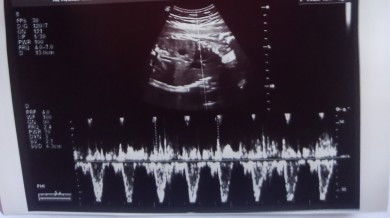

Excited to become a mum

that's the upper body! your baby's head and neck is on the right and your baby is facing upwards